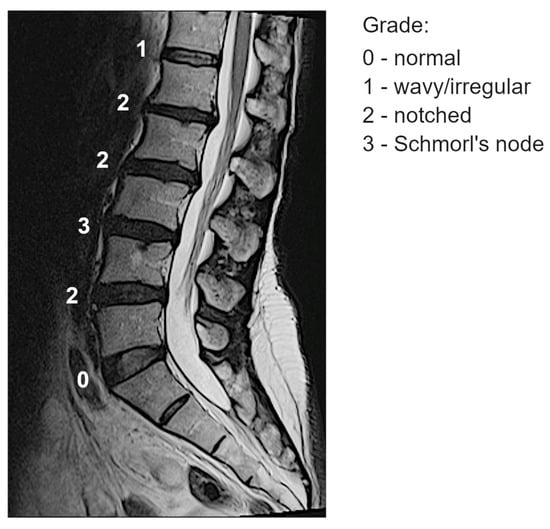

- Grade 0 (“normal”): No lesions are visually identified in the sagittal MRI slices encompassing the intervertebral space.

- Grade 1 (“wavy/irregular”): No specific lesions are detectable in the intervertebral space, but at least one endplate exhibits an altered shape compared to the typical curvature of a healthy intervertebral space. The endplate may appear wavy or irregular.

- Grade 2 (“notched”): A small lesion is visible in at least one sagittal MRI slice. The lesion has a V-shaped or circular appearance and is present on one or both endplates, suggesting small defects or indentations.

- Grade 3 (“Schmorl’s node”): A deep focal defect is observed in the vertebral endplate, characterized by a smooth margin and rounded appearance. Schmorl’s nodes involve disc tissue protruding through the endplate into the vertebral marrow.